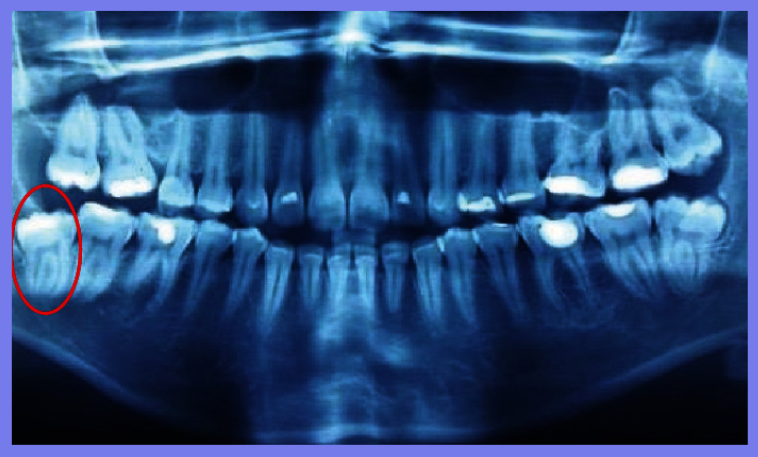

在医院对患者进行检查,除全身健康状况外,临床评估还显示右侧面部剧烈疼痛和肿胀、下颌轮廓明显凹陷、张口受限、咬合不正、前段骨性活动性差、右下颌第三磨牙缺失。计算机断层扫描 (CT) 扫描和 3D 重建分别显示直角部位下颌节段的牙槽骨连续性断裂和横向移位的髁突 (远端) 碎片。水肿消退后,在全身麻醉下进行下颌骨骨折治疗。外科医生进行口内切开复位,重新定位节段,并使用两块钛板和六毫米螺钉防止碎片移动并确保骨一期愈合。在同一手术中,对侧上下第三磨牙也被拔除。